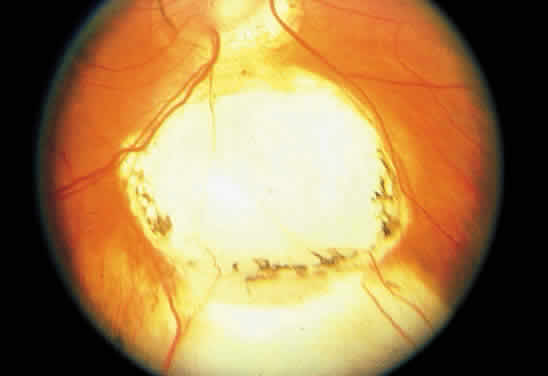

MORNING GLORY DISC ANOMALY

The morning glory optic disc anomaly appears ophthalmoscopically as an enlarged excavated disc with white, fibroglial-appearing tissue located at its center; an elevated, subretinal peripapillary annulus of chorioretinal pigmentary changes encircles the disc (Fig. 11). This congenital abnormality has been likened to the morning glory flower, from which it derives its name.131 Most cases are unilateral, and visual acuity most often falls into the 20/100 (6/30) to hand-motion range.131,132 Retinal detachment is seen in over one third of cases, the etiology of which is uncertain.132,133 These detachments connect to the optic nerve head and usually are confined to the posterior pole.131,134 The mechanism may involve a retinal break in the tissue within the optic disc anomaly, which provides a communication for fluid between the vitreous cavity and the subretinal space,135–137 or from an abnormal communication between the subarachnoid space surrounding the optic nerve and the subretinal space.133,138 Most cases are managed with plana vitrectomy, laser photocoagulation, and intravitreal gas or silicone oil tamponade.135,137,139

Fig. 11. Morning glory optic disc anomaly. The retinal vessels enter and leave the nerve head at its margins.